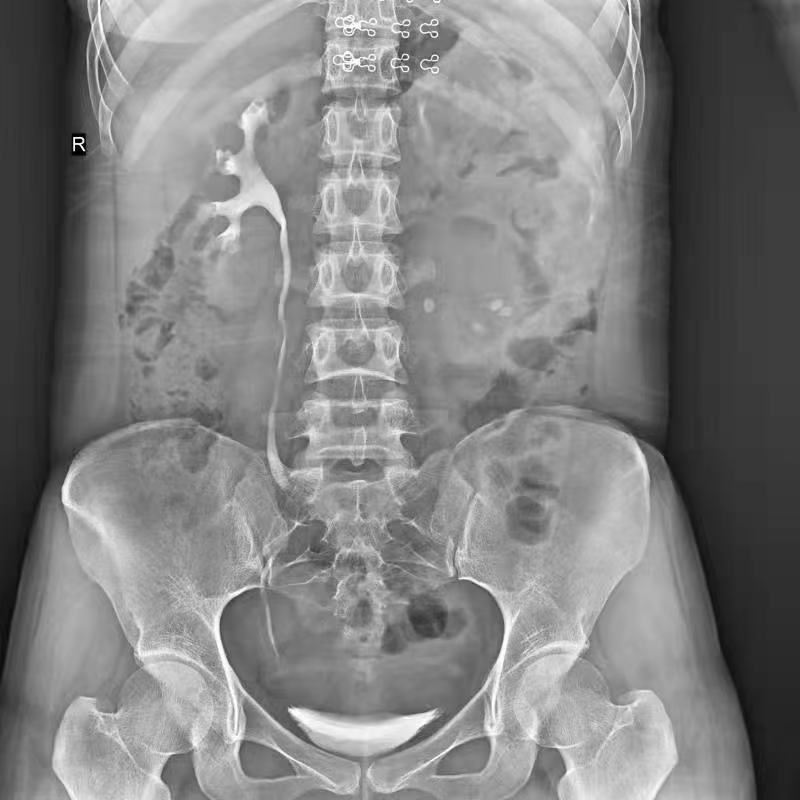

普利德醫(yī)療自主研發(fā)的新一代數(shù)字化X線透視攝影系統(tǒng),可應用于DR攝影、數(shù)字透視、數(shù)字造影以及可視化精準DR拍片等多種臨床X線檢查領域。

● 17*17英寸的超高清像素動態(tài)平板探測器,更大的視野范圍,無需移動即可觀察整個動態(tài)過程,避免拖尾、噪聲對圖像的影響;

● 高效動態(tài)平板技術,圖像不會有幾何畸變,提供高分辨率和精確的圖像,為醫(yī)生臨床診斷提供精準依據(jù);

點片裝置移動范圍大,無需患者移動就能完成全身各部位的檢查;

床面橫向移動,輕松實現(xiàn)機動人不動。